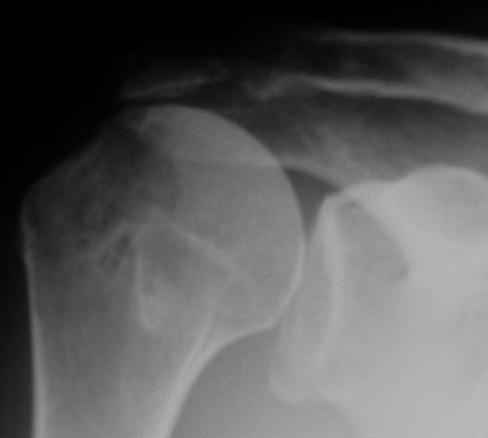

Верхний подвывих в такой ситуации может быть проявлением ротаторной артропатии, как следствия более массивного, чем частичный разрыв сухожилия надостной мыщцы, повреждения вращательной манжеты. И значит нужно думать о том, насколько полно восстановлена манжета, адекватно ли был расценен объем ее повреждения. Что за шов применялся? Якорных винтов не видно. И почему гипсовая иммобилизация? Есть прекрасные надувные отводящие подушки, позволяющие ранние движения.

В качестве примера - снимки до и после восстановления целостности вращательной манжеты после 3-хмесячной давности полного разрыва. Видно, что верхний подвывих устранен.